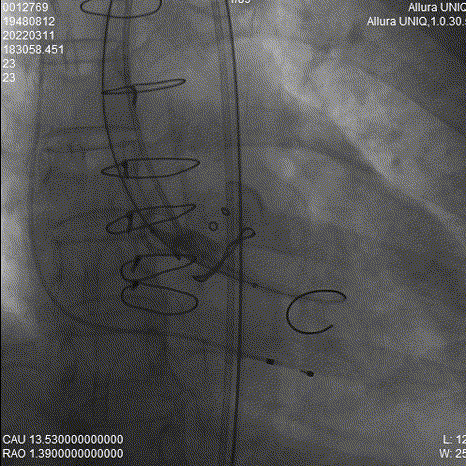

瓣膜释放过程